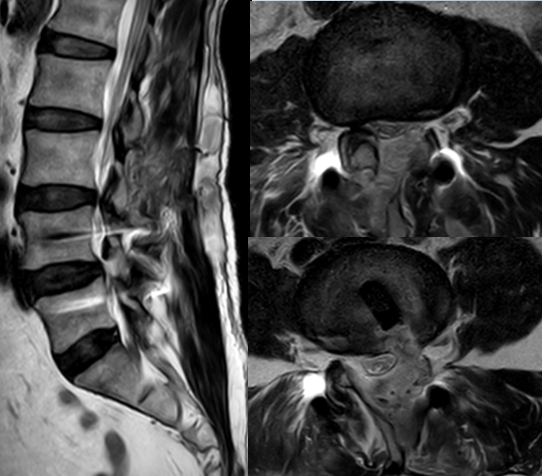

九、类脊髓高压综合征

病例

女,51岁。

主诉:腰疼伴左下肢疼痛麻木4个月。

既往史:椎间孔镜下椎间盘切除术(L4-5)。

术前

术中:术中硬膜破裂,灌洗液压力30mmHg,硬膜破裂后1小时出现血压升高,心率加快,手术持续2小时。

术后:延迟苏醒,拔管困难,转ICU,6小时候拔管神志恢复正常。

术后

思考与建议:

警惕硬膜损伤

全麻下早期表现:血压升高,心率加快

尽快结束手术或中转开放手术

有条件情况下给予硬膜修补

多数患者预后良好